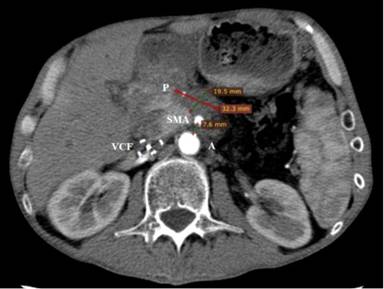

The control CT scan two months after the HIFU procedure confirmed coagulative necrosis with no contrast enhancement of the primary tumor with mean size of the longest diameter 32 mm (Figure 5). The patient’s GHS improved to 33, and his pancreatic pain decreased to 42. At the sixth month of follow-up after the HIFU ablation his GHS improved to 42 and the pancreatic pain was significantly reduced to 17. According to the VAS, the pancreatic pain was reduced from 7 before HIFU to 2 out of 10. The digestive symptoms improved from 50 before to 0 and the bowel habits from 67 to 33. In this period the BMI increased from 14.9 to 18.1 kg/m2.

Figure 5. Control contrast enhanced CT (2 months after the HIFU treatment). The ablated tumor mass (P) shrunk to 32 mm in size and it was not enhancing. The distance between the aorta (A) and superior mesenteric artery (SMA) was the same (8 mm). |

Twelve months after the HIFU ablation, CT revealed a decreased tumor size to 18 mm (Figure 6). An objective anatomical landmark, confirming the shrinkage of the formation during the patient follow-up was the distance between the aorta and the superior mesenteric artery. Before HIFU ablation the distance was 8.2 mm, and 12 months later it reached 23 mm (Figures 3 and 6). The control CT also showed remarkable reduction of the liver metastases (Figure 2c). The quality of life evaluated by the same EORTC instruments remained stable.